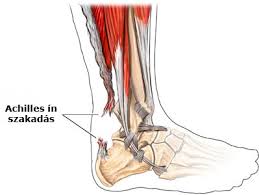

Az Achilles-ín krónikus gyulladása és sérülése

Az Achilles-ín sérülése igen gyakran fordul elő középkorú férfiaknál, a sportolók negyedik leggyakoribb sérülése. Gyakori jelenség, hogy az ín sérülése az aktív sport pályafutás után következik be, hobbi sportolás során. Ennek oka, hogy ahosszú éeken át tartó aktív sport, jelentős terhelés miatt az ín állományában degenerációnak nevezett elváltozások mennek vége, emiatt az ín szakító szilárdsága ellenállóképessége csökken és egy váratlan, gyakran banális mozdulatra elszakad.

Sokkal gyakoribb jelenség az Achilles ín krónikus fájdama, érzékenysége, gyakran terhelésre megfigyelhető duzzana, az ín tapadádnál a sarokcsonton fájdalmas dudor megjelenése. Ezt a tünetggyüttest Achyllodyniának nevezzük.

Az Achillodynia kezelése konzervatív, pihenés, a terhelés csökkentése, lokálisan krémek alkalmazása, hűtés, fizikoterápi, sarokemelő szilikonos betét használat. Kiváló eredményeket ad a lökéshullám kezelés, az orvosi kollagén ijekció és a thrombocytábandús plazma beadása.

Ha ezek a kezelési módok nem vezetnek eredményre műtét is szóba jön, ilyenkor a heges, szűk ínhüvelyt bemetsszü és az ínra nehezedő nyomást csökkentjük.

Az Achiiles ín sérülés ellátása mindenképpen műtéti, és időfaktorhoz kötött. Sürgősséget igényel, mert a szakadt ínban hamar megindul a leépülés, egy része felszívódik, később hegesedésnek, zsugorodásnak indul, ami miatt az egyszerű ínvarrat már nem elég. Ilyenkor a rövidült, vagy rossz állományú inat helyreállítani, csak plasztikai megoldással lehet. t rehabilitáció, és a gyógytorna.